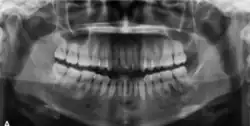

Panoramic radiograph showing a radiopaque lesion surrounded by a radiolucent rim around the root of left first and second mandibular molar [25]

In its early stages, central ossifying fibroma (COF) appears as a small, well-defined radiolucent lesion due to its fibrous tissue content. Differential diagnoses at this stage include periapical pathology, central giant cell granuloma, and ameloblastoma.[22][23] As the lesion matures, it exhibits a mixed radiolucent-radiopaque appearance due to progressive calcification.[22] At this stage, it should be differentiated from other mixed jaw lesions such as fibrous dysplasia, calcifying epithelial odontogenic tumour, adenomatoid odontogenic tumour, and condensing osteitis.[22] In its mature form, COF may appear predominantly radiopaque, resembling lesions like odontomas, osteoblastomas, or osteosarcomas radiographically.

COF typically presents with well-defined, smooth, and often corticated borders. As a central lesion, it originates within the medullary bone and expands concentrically in all directions.[24] With growth, it may cause tooth displacement, root resorption, inferior displacement of the mandibular canal, and loss or alteration of the lamina dura of adjacent teeth.[25]

In conclusion, COF most commonly occurs in the mandible and expands from a central epicenter. Radiographically, it presents as a well-defined mixed-density lesion,[26] and Cone Beam CT (CBCT) plays a crucial role in its accurate diagnosis and assessment.